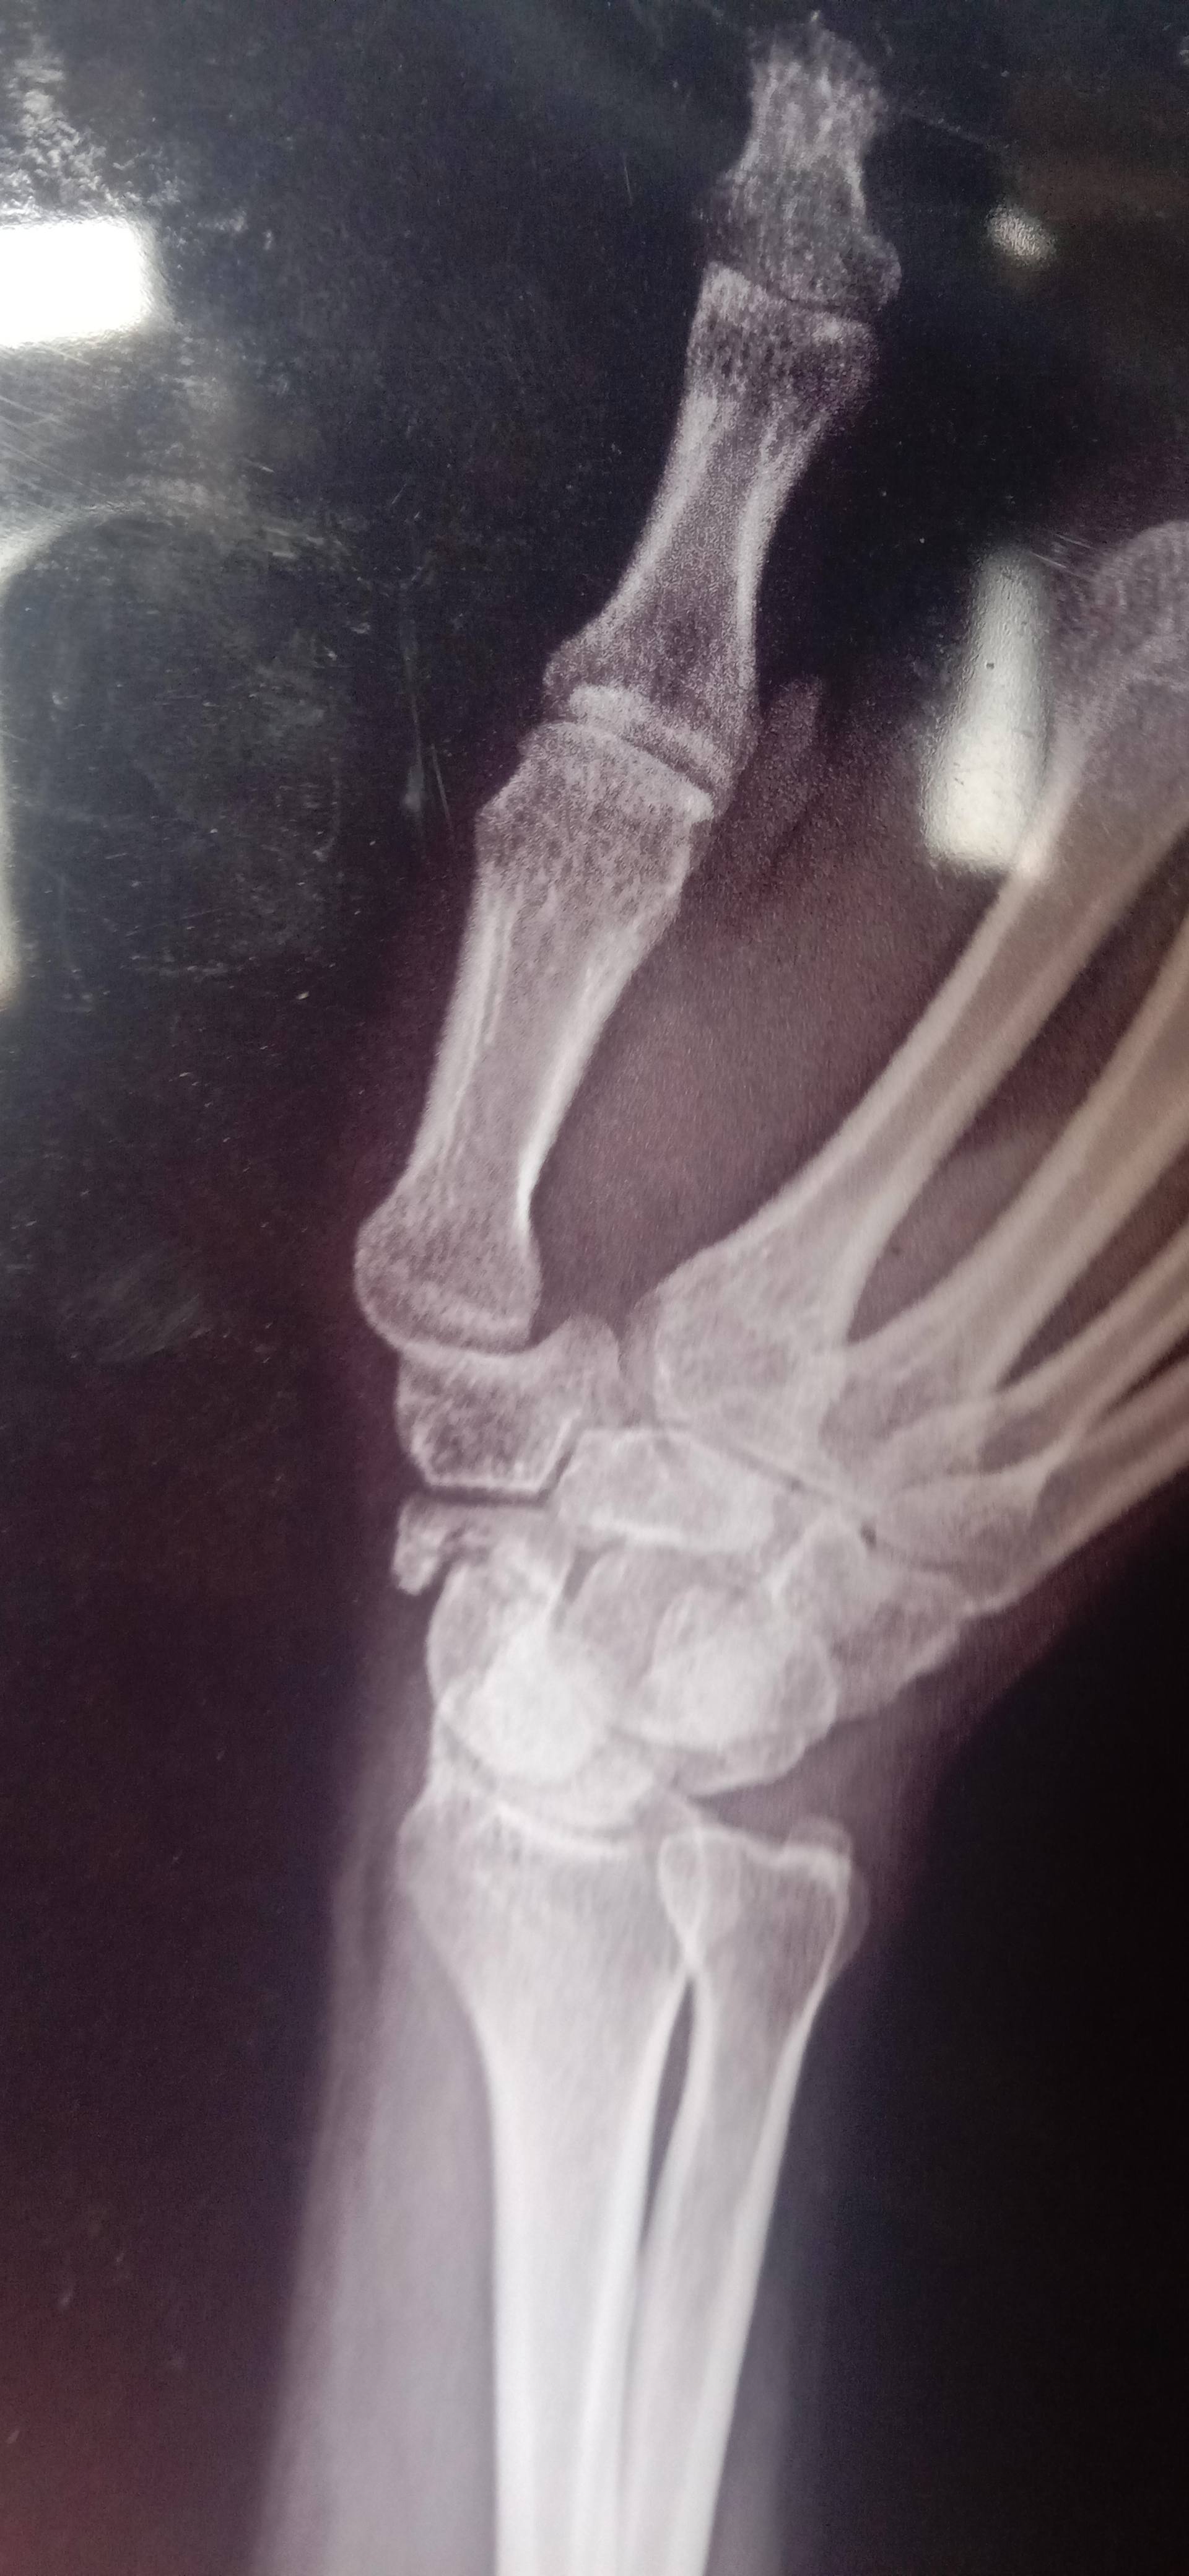

Hlo sir mara scaphoid ka fracture ha